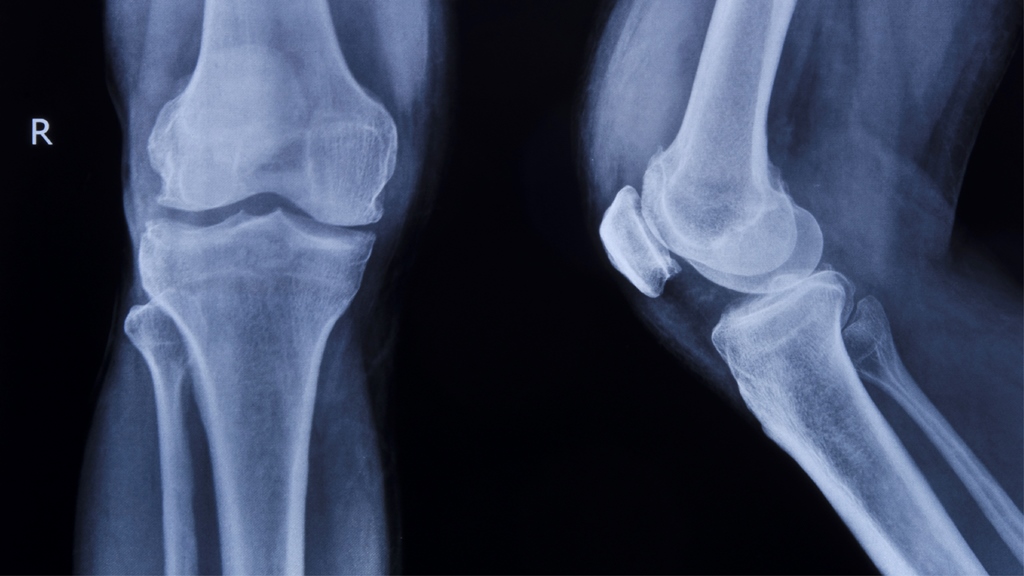

María del Pilar, es una Ortopedista muy especial, ya que su especialidad es la Ortopedia y traumatología en niños, una actividad que le permitió soñar con independizarse y crear su imagen, el desafío era construir su marca con los ingredientes que más la representan: energía, amor y cuidado con el que asume su formación. Este es el desarrollo de su marca.